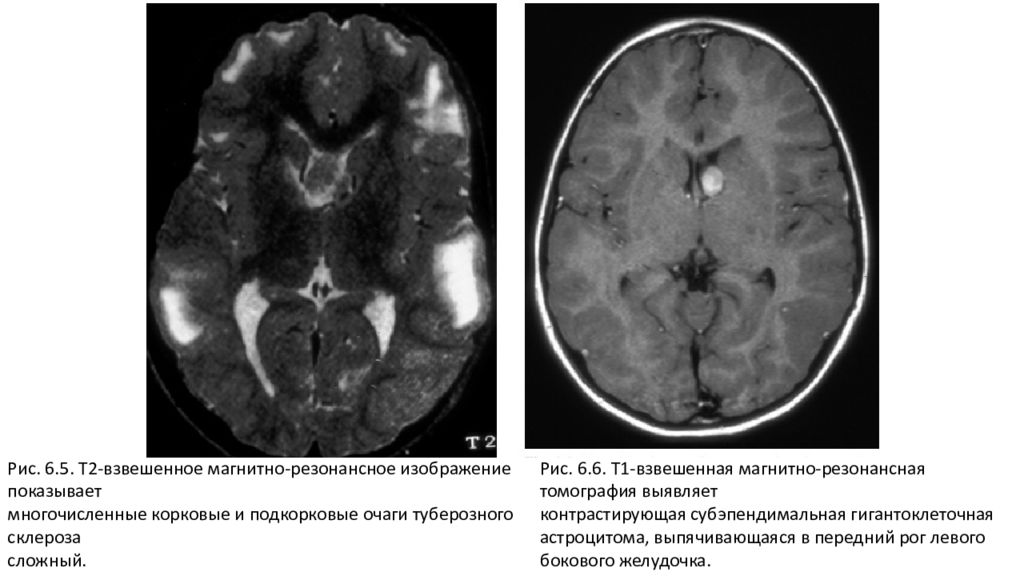

Субэпендимально слева киста

Субэпендимально слева киста 115 фотографий